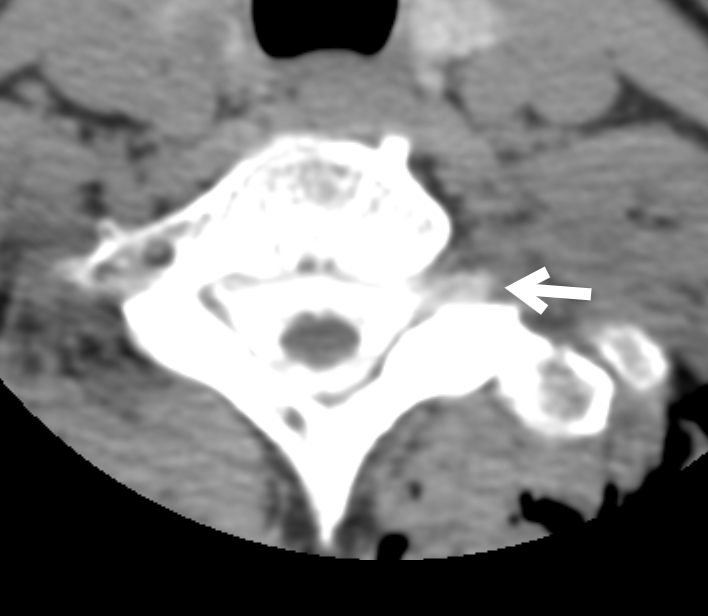

当院では腰椎穿刺による圧測定(硬膜外生食注入含む)と脊髄CTミエログラフィーが可能です。右図は当院で診断した漏出の所見です。